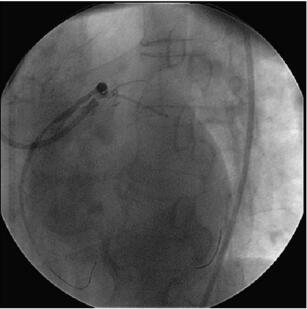

冠状动脉造影(图058‐2、图058‐3)多体位造影显示:冠脉呈右冠优势型,L M开口见90%局限性狭窄;LAD 管壁不光滑,近段见90%局限性狭窄,D1 开口后次全闭塞,中段见85%弥漫性病变,远端血流TI MI 3 级;LCX 管壁不光滑,远端90%局限性狭窄,OM1分叉处Ⅰ型分叉病变,最窄处约80%,远端血流TI MI 3 级;RCA 管壁欠光滑,远段见85%偏心性狭窄,PDA 开口前分叉病变,最窄处约95%,远端血流TI MI 3 级。

图058‐2 冠状动脉造影

图058‐3 冠状动脉造影